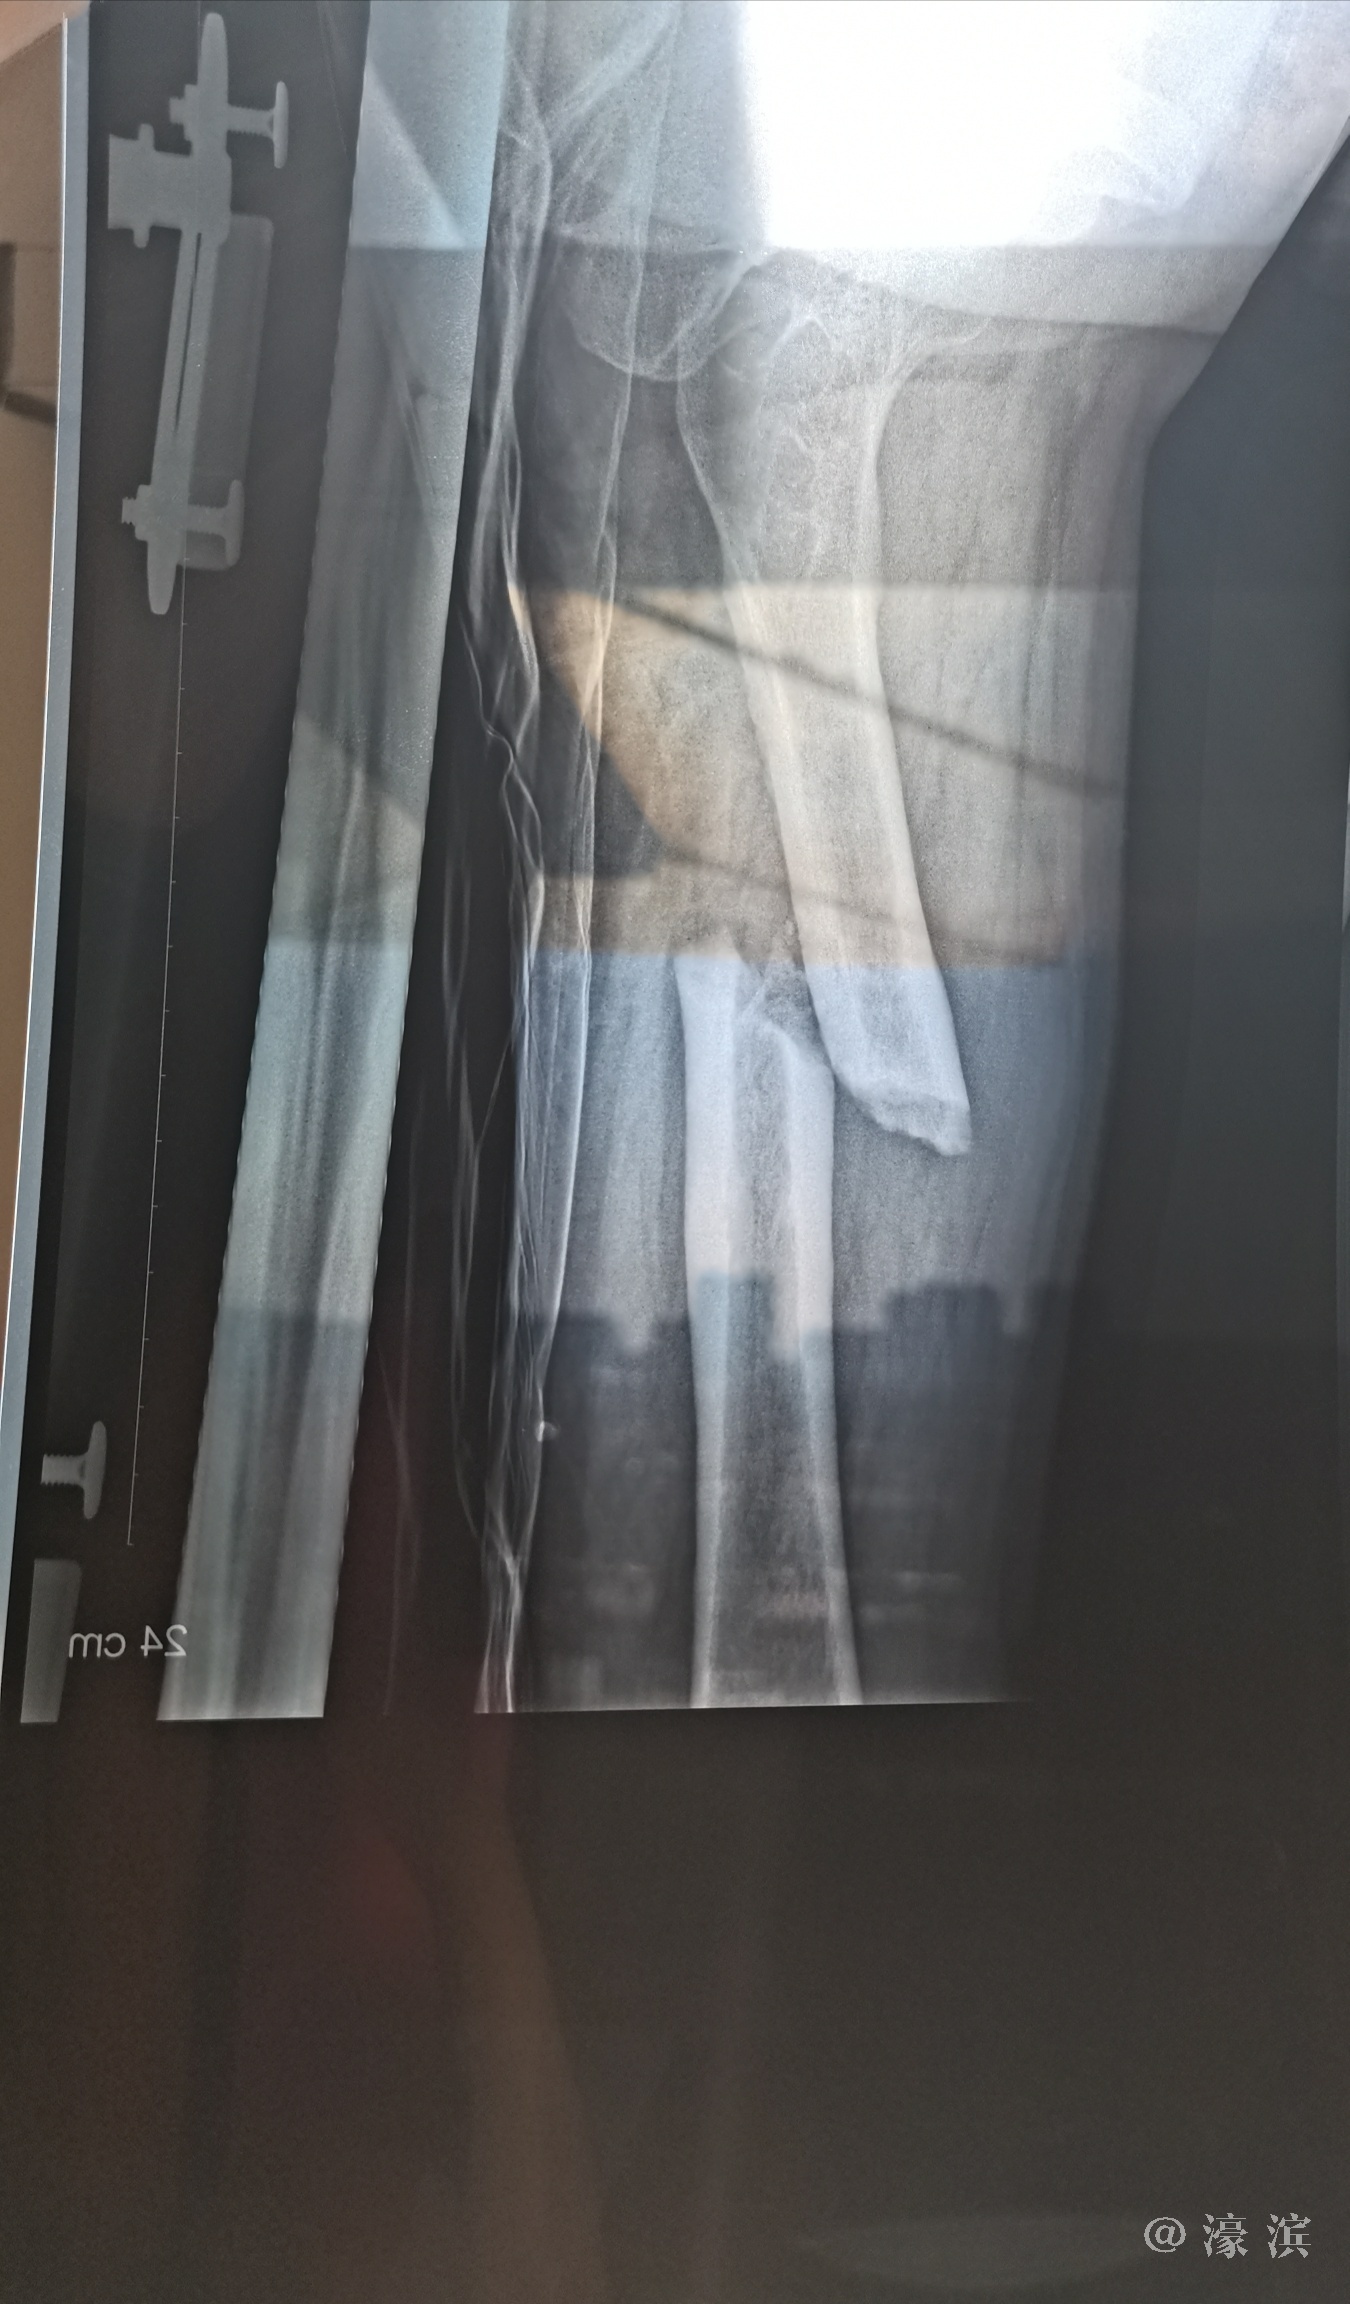

医院X光片显示我母亲股骨骨折,完全断裂错位,令人触目惊心!